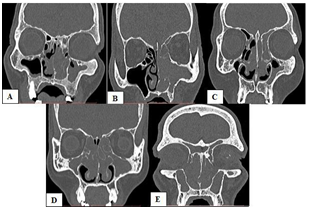

The identification of anatomic variants and staging was accomplished by the author and co-author. The following are the anatomic variations of the paranasal sinuses with implications in sinus drainage (Figure 1)

Agger Nasi cell-an anteriorly located extramural air cell not confined within the ethmoid bone. It is immediately anterior to the insertion of the middle turbinate forming the floor of the frontal recess.

Figure 1 Anatomic variations on paranasal sinus CT scan; Agger nasi cell (A) Infraorbital (Haller) cell and Paradoxical middle turbinate (B) Concha bullosa (C) Everted uncinate process (D) Septal deviation (E).

Infraorbital (Haller) cell-an ethmoid air cell that extend along the medial floor of the orbit. Paradoxical middle turbinate-convexity of the middle turbinate is directed laterally. Concha bullosa-an aerated middle turbinate. Everted uncinate process-an abnormally projecting uncinate process medially toward middle turbinate.

Septal deviation-buckling in the nasal septum resulting in concavity on the other side of the septum and narrowing on the contralateral side.